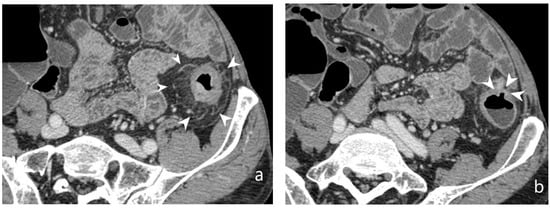

5.2. Fibro-Stenotic Subtype